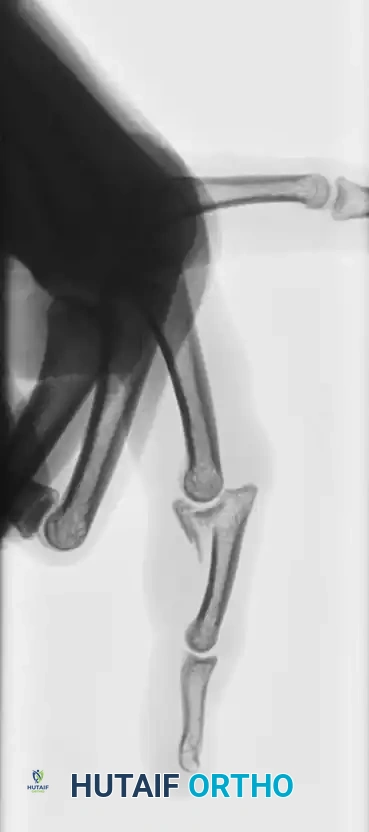

Fracture-Dislocations of the Proximal Interphalangeal (PIP) Joint

Fracture-dislocations at the PIP joint typically result in an unstable dorsal displacement of the middle phalanx. This is caused by the disruption of the volar plate's attachment to the volar lip of the middle phalanx, often accompanied by impaction of the articular surface.

Treatment is strictly dictated by the percentage of articular surface involved and the degree of comminution.

1. Large Volar Fragment (>50% of Joint Surface)

If a large, single volar fragment involving more than 50% of the joint surface is present, the joint is highly unstable. Open reduction and internal fixation (ORIF) is required. This can be achieved with miniature lag screws, K-wires, or a wire loop pull-out technique to secure the fragment and restore the volar buttress.